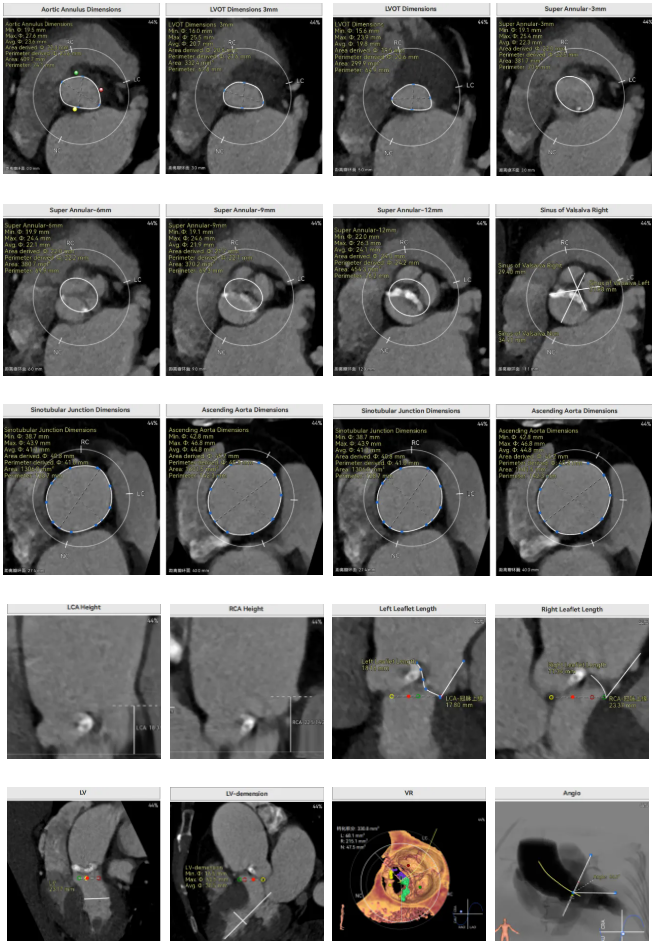

术前CT

Type1型二叶瓣,L-R融合,瓣叶轻度钙化,主要分布在无窦瓣叶边缘处,主动脉瓣环径23.6mm,LVOT20.6mm,呈收口型;双侧冠脉开口高度可,窦部空间大,VTC距离够,预估冠脉低风险,STJ、升主动脉内径增宽。右冠起源于左窦;主动脉水平夹角65.6°,横位心,主动脉弓角、弓距可。外周入路无明显迂曲,无明显钙化,双侧股动脉内径可,均能通过20F大鞘,右股低分叉。

推荐右侧股动脉为主入路,左侧股动脉为辅助入路,使用20F大鞘,推荐选择AV26瓣膜,备AV23瓣膜,18mm球囊预扩/不预扩,最终理想位置瓣下2mm。